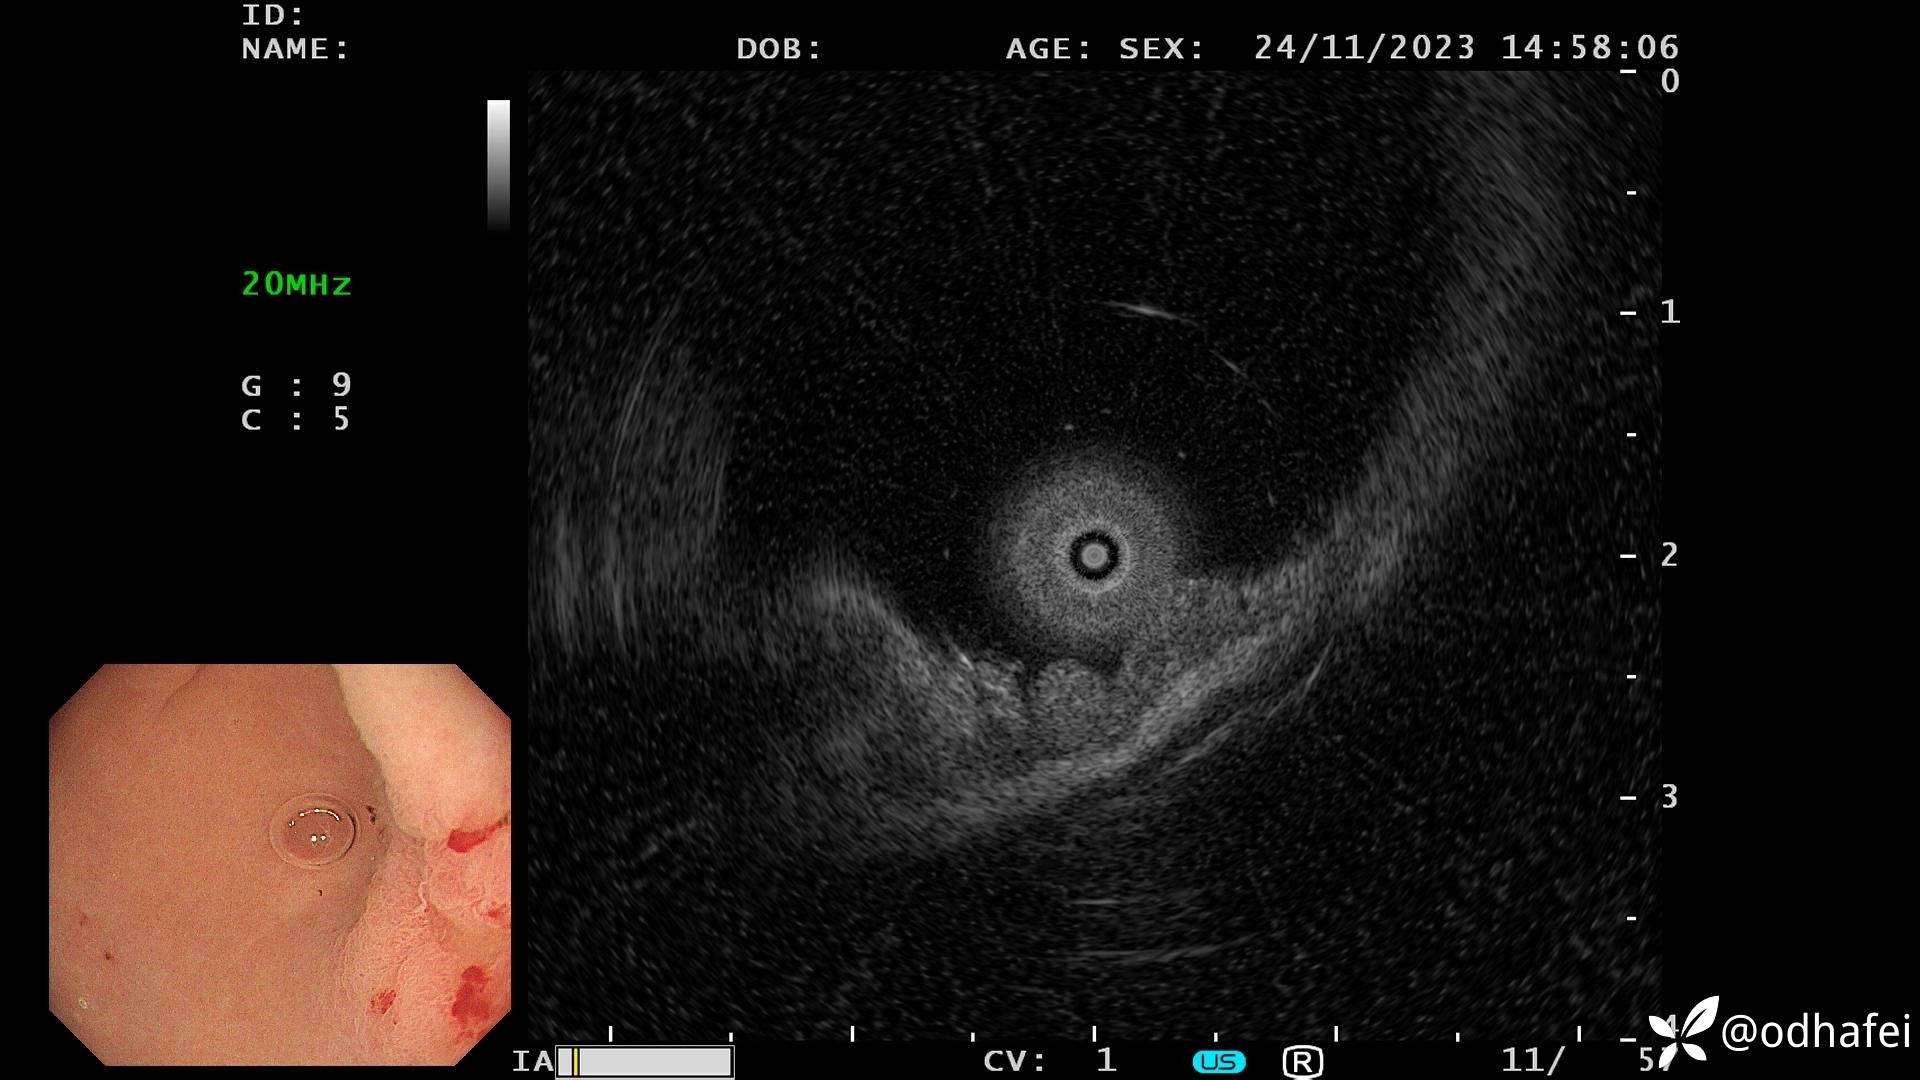

最近做的一例胃体早癌,通过术前的放大及染色,性质判断为肿瘤性病变,考虑高分化管状腺癌可能性大,充吸气实验及超声内镜检查综合判断病变局限于黏膜层,并行ESD治疗。